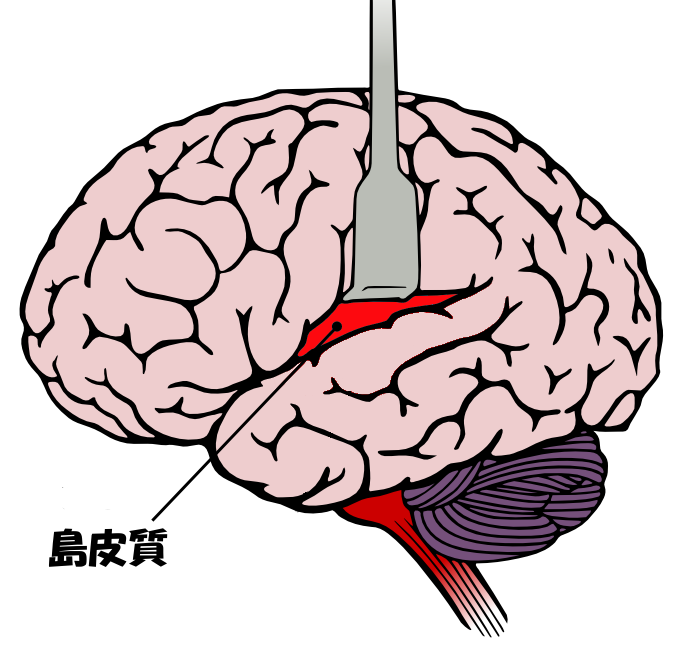

島皮質 Wikipedia